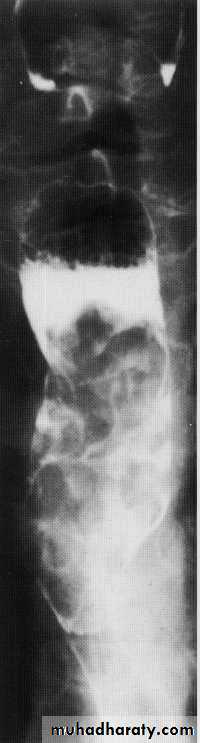

Tertiary contractions